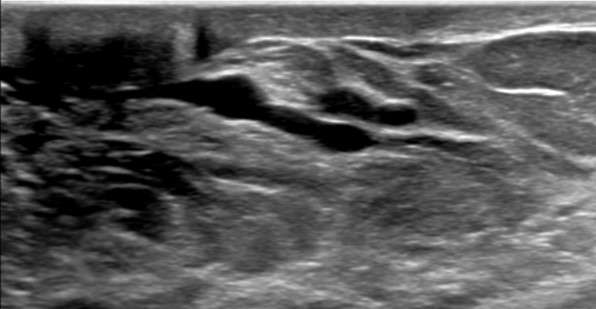

1. Hypoechoic tubular structures measuring larger than 2 mm in diameter or 3 mm in diameter at the ampulla. These dilated ducts may be exhibit anechoic intraductal features secondary to simple fluid or low-level internal echoes secondary to intraductal debris.

Case: Breast Ductal Anatomy and Function Figure 1

Figure 1: Ultrasound demonstrating benign retroareolar duct ectasia